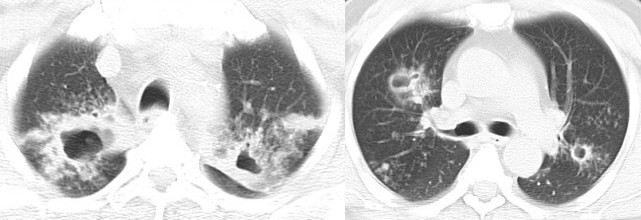

病例3:肺腺癌

这个病人表现为两肺多灶、多斑片的实变,在右中下叶肺可以看到实变,仔细看两肺还有一些小点状。CT表现为右上叶明显实变,实变外周有小结节影,更低的层面可以看到右中叶明显实变影,另有磨玻璃影,右下叶有些实变影以及小叶中心的结节。在对侧,主要更多的是一些细小的点状。这个病人低烧,刚开始会想到炎症,但是这个病人不是常见的炎症表现,第一是因为边界比较清楚,第二是由于外周伴有小结节,所以这时就要小心,说明这个病变不是急性,要想到炎症之外的病变。这个病人最后诊断为肺腺癌。